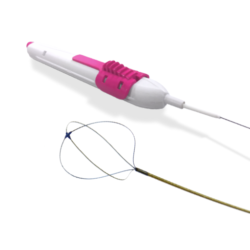

ENDOFIRM – PolyUrethane Double Loop Ureteral Stents

Stiff Kit – With Nitinol Guide Wire